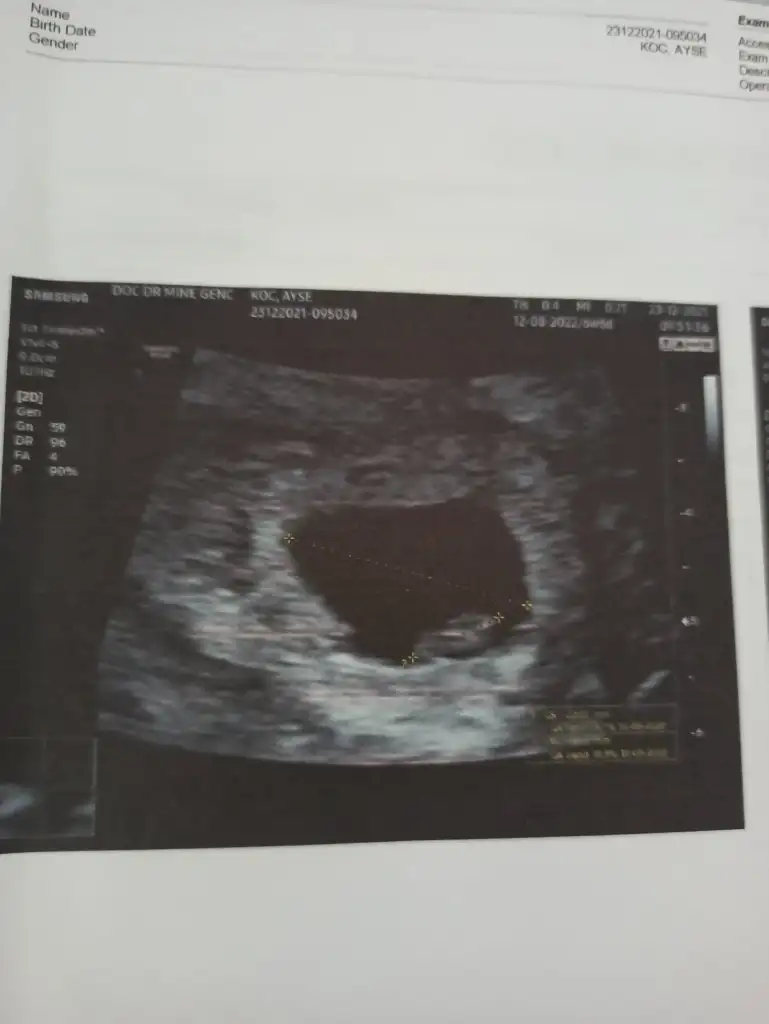

ozele gidiyorum aslında kizlarda 12. haftdada bende öğrenmiştim kesin konusmuslardi o zaman usg var ekliyorum yorumlarsanız sevinirim en azından kafam rahatlasin istiyorum ikilemde kalmak kötü hissediyor

Renkli usg ye doktor bisey demedi mi bacaklarını toplamış gibi tam anlaşılmıyor

bacak arası hep sim siyah renkli olanda da bulanık anlayamadık doktorda o yuzden emin olamadı. sanırım daha bekletmek istiyor biraz daha merak edin diyor 😀hayırlısı nasılsa oyle olsun inşallah sağlıkla hayırla dogsunlar bütün bebekler